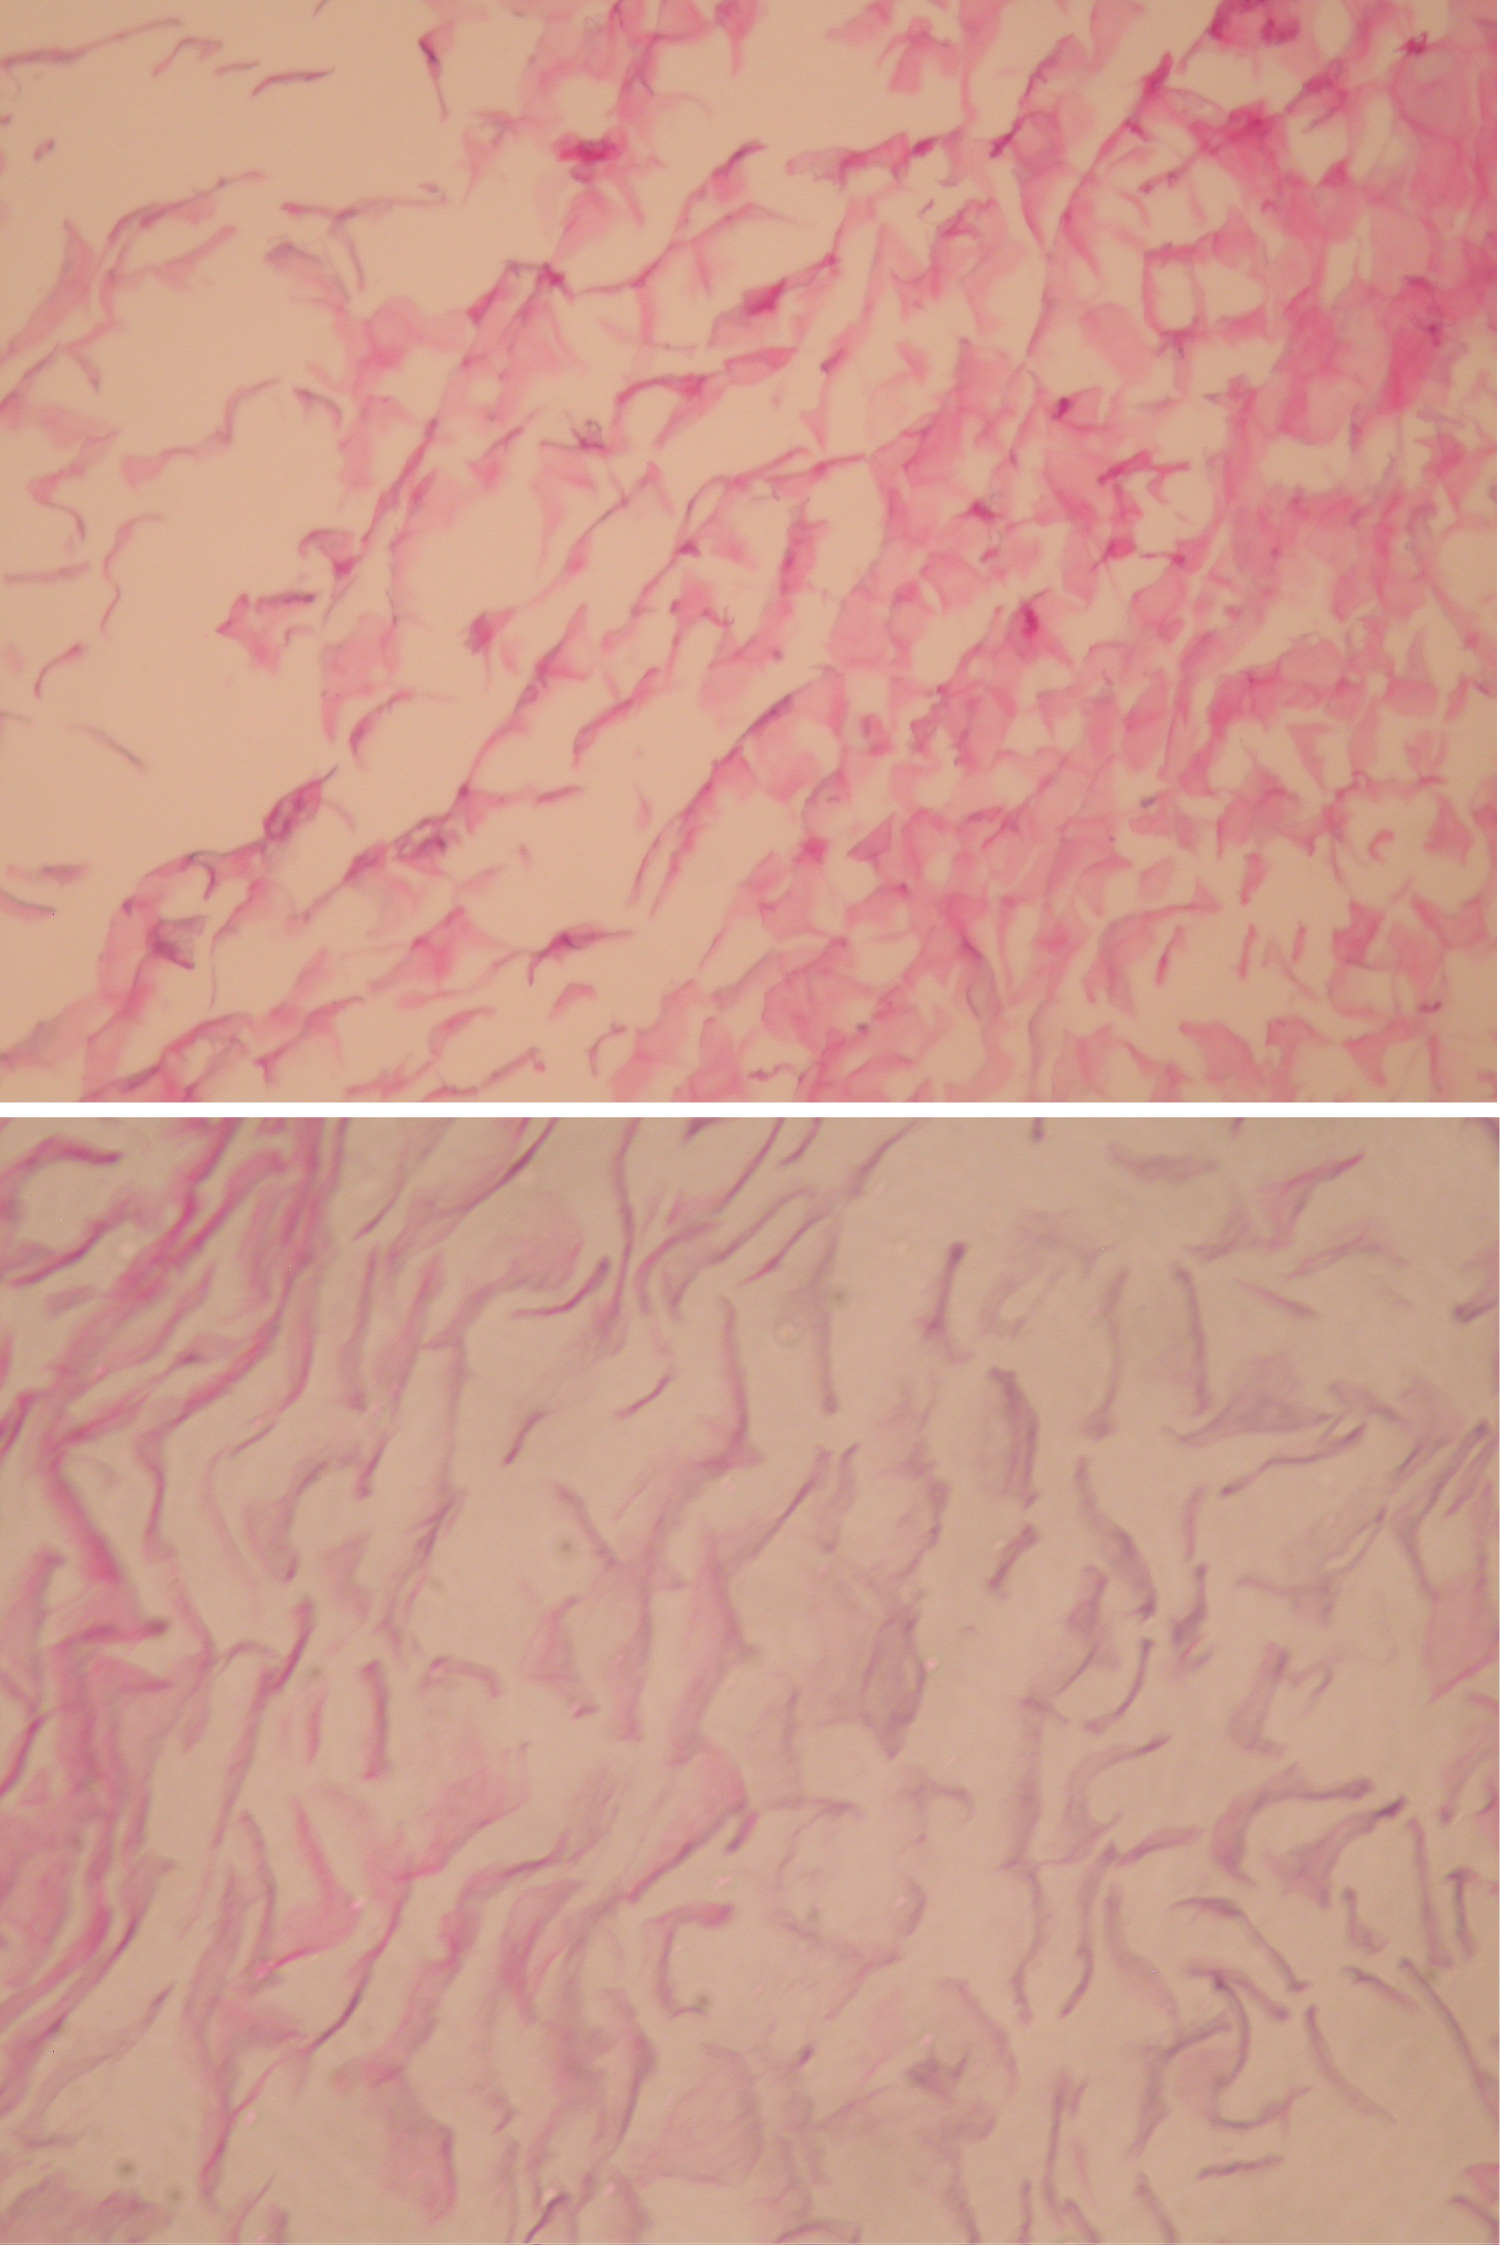

In our case, the patient was an adult, diagnosed with a palpable mass at his occiput, which was proven to be an intraosseous epidermoid cyst, compressing on the confluence of the sinuses, causing increased ICP and visual symptoms and papilloedema. It is advisable for scalp lesions, especially overlying important anatomical structures, to perform brain imaging, before attempting excision (Figure 1, Figure 2, Figure 3 and Figure 4).

Figure 2: Axial MRI shows typical features of epidermoid. Mixed signal lesion on T1 (A). No enhancement after injection of gadolinium (B). Predominantly high signal on T2 (C). Slightly heterogenous signal on the T2 flair, higher than cerebrospinal fluid (D). Striking high signal on the diffusion weighted images (DWI) (E) with corresponding low signal on the apparent diffusion coefficient (ADC) map (F) consistent with restricted diffusion. View Figure 2